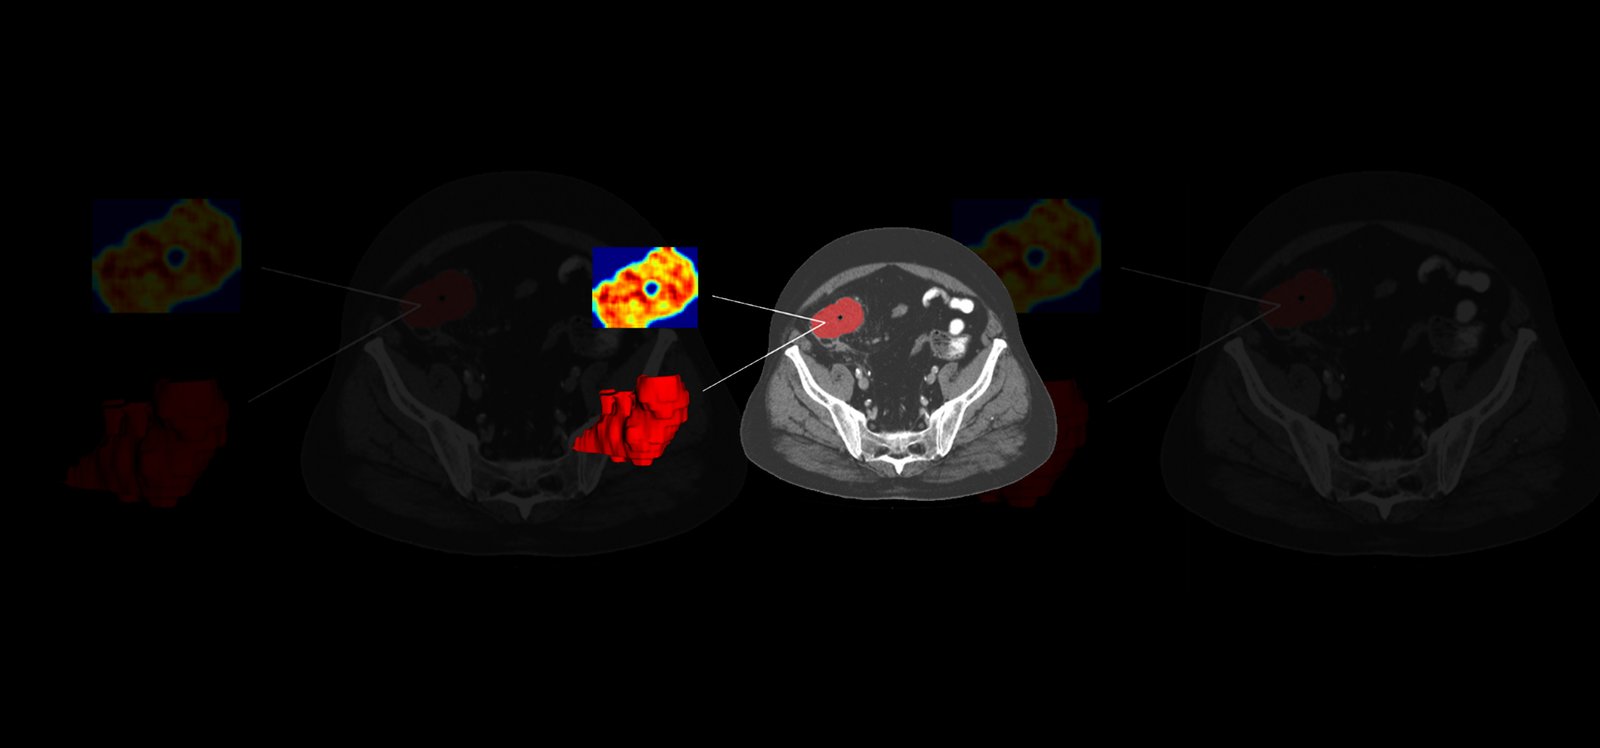

Following a collaborative design, we collected retrospective multi-center real-world data (RWD) from a large sample of patients with diagnoses confirmed by traditional methods. The RWD included clinical data, liquid biopsy, and SoC CT scans. A 3D segmentation of the tumoral tissue was performed, and textures, deep features, and fractal dimensions parameters were extracted. Once all of these quantitative imaging biomarkers were obtained, several AI-based classification models were trained combining the imaging features with liquid biopsy and clinical data to predict early relapse in patients and classify patients with low and high risk. The analysis pipeline generated was integrated into QP-Discovery® platform, creating an end-to-end AI tool.

By merging clinical data with radiomics, fractal, and deep features, the AI model provided a high and increased accuracy of 87.9% (CI 95%: 67.7–100) when compared to clinical variables alone (60%, CI 95%: 30–90) in the prediction of relapse. The most accurate AI-based model is expected to be obtained by combining radiomic features with RWD to predict potential patients to be relapsed, leading to the selection of personalized treatments that improve response over current standard therapies.